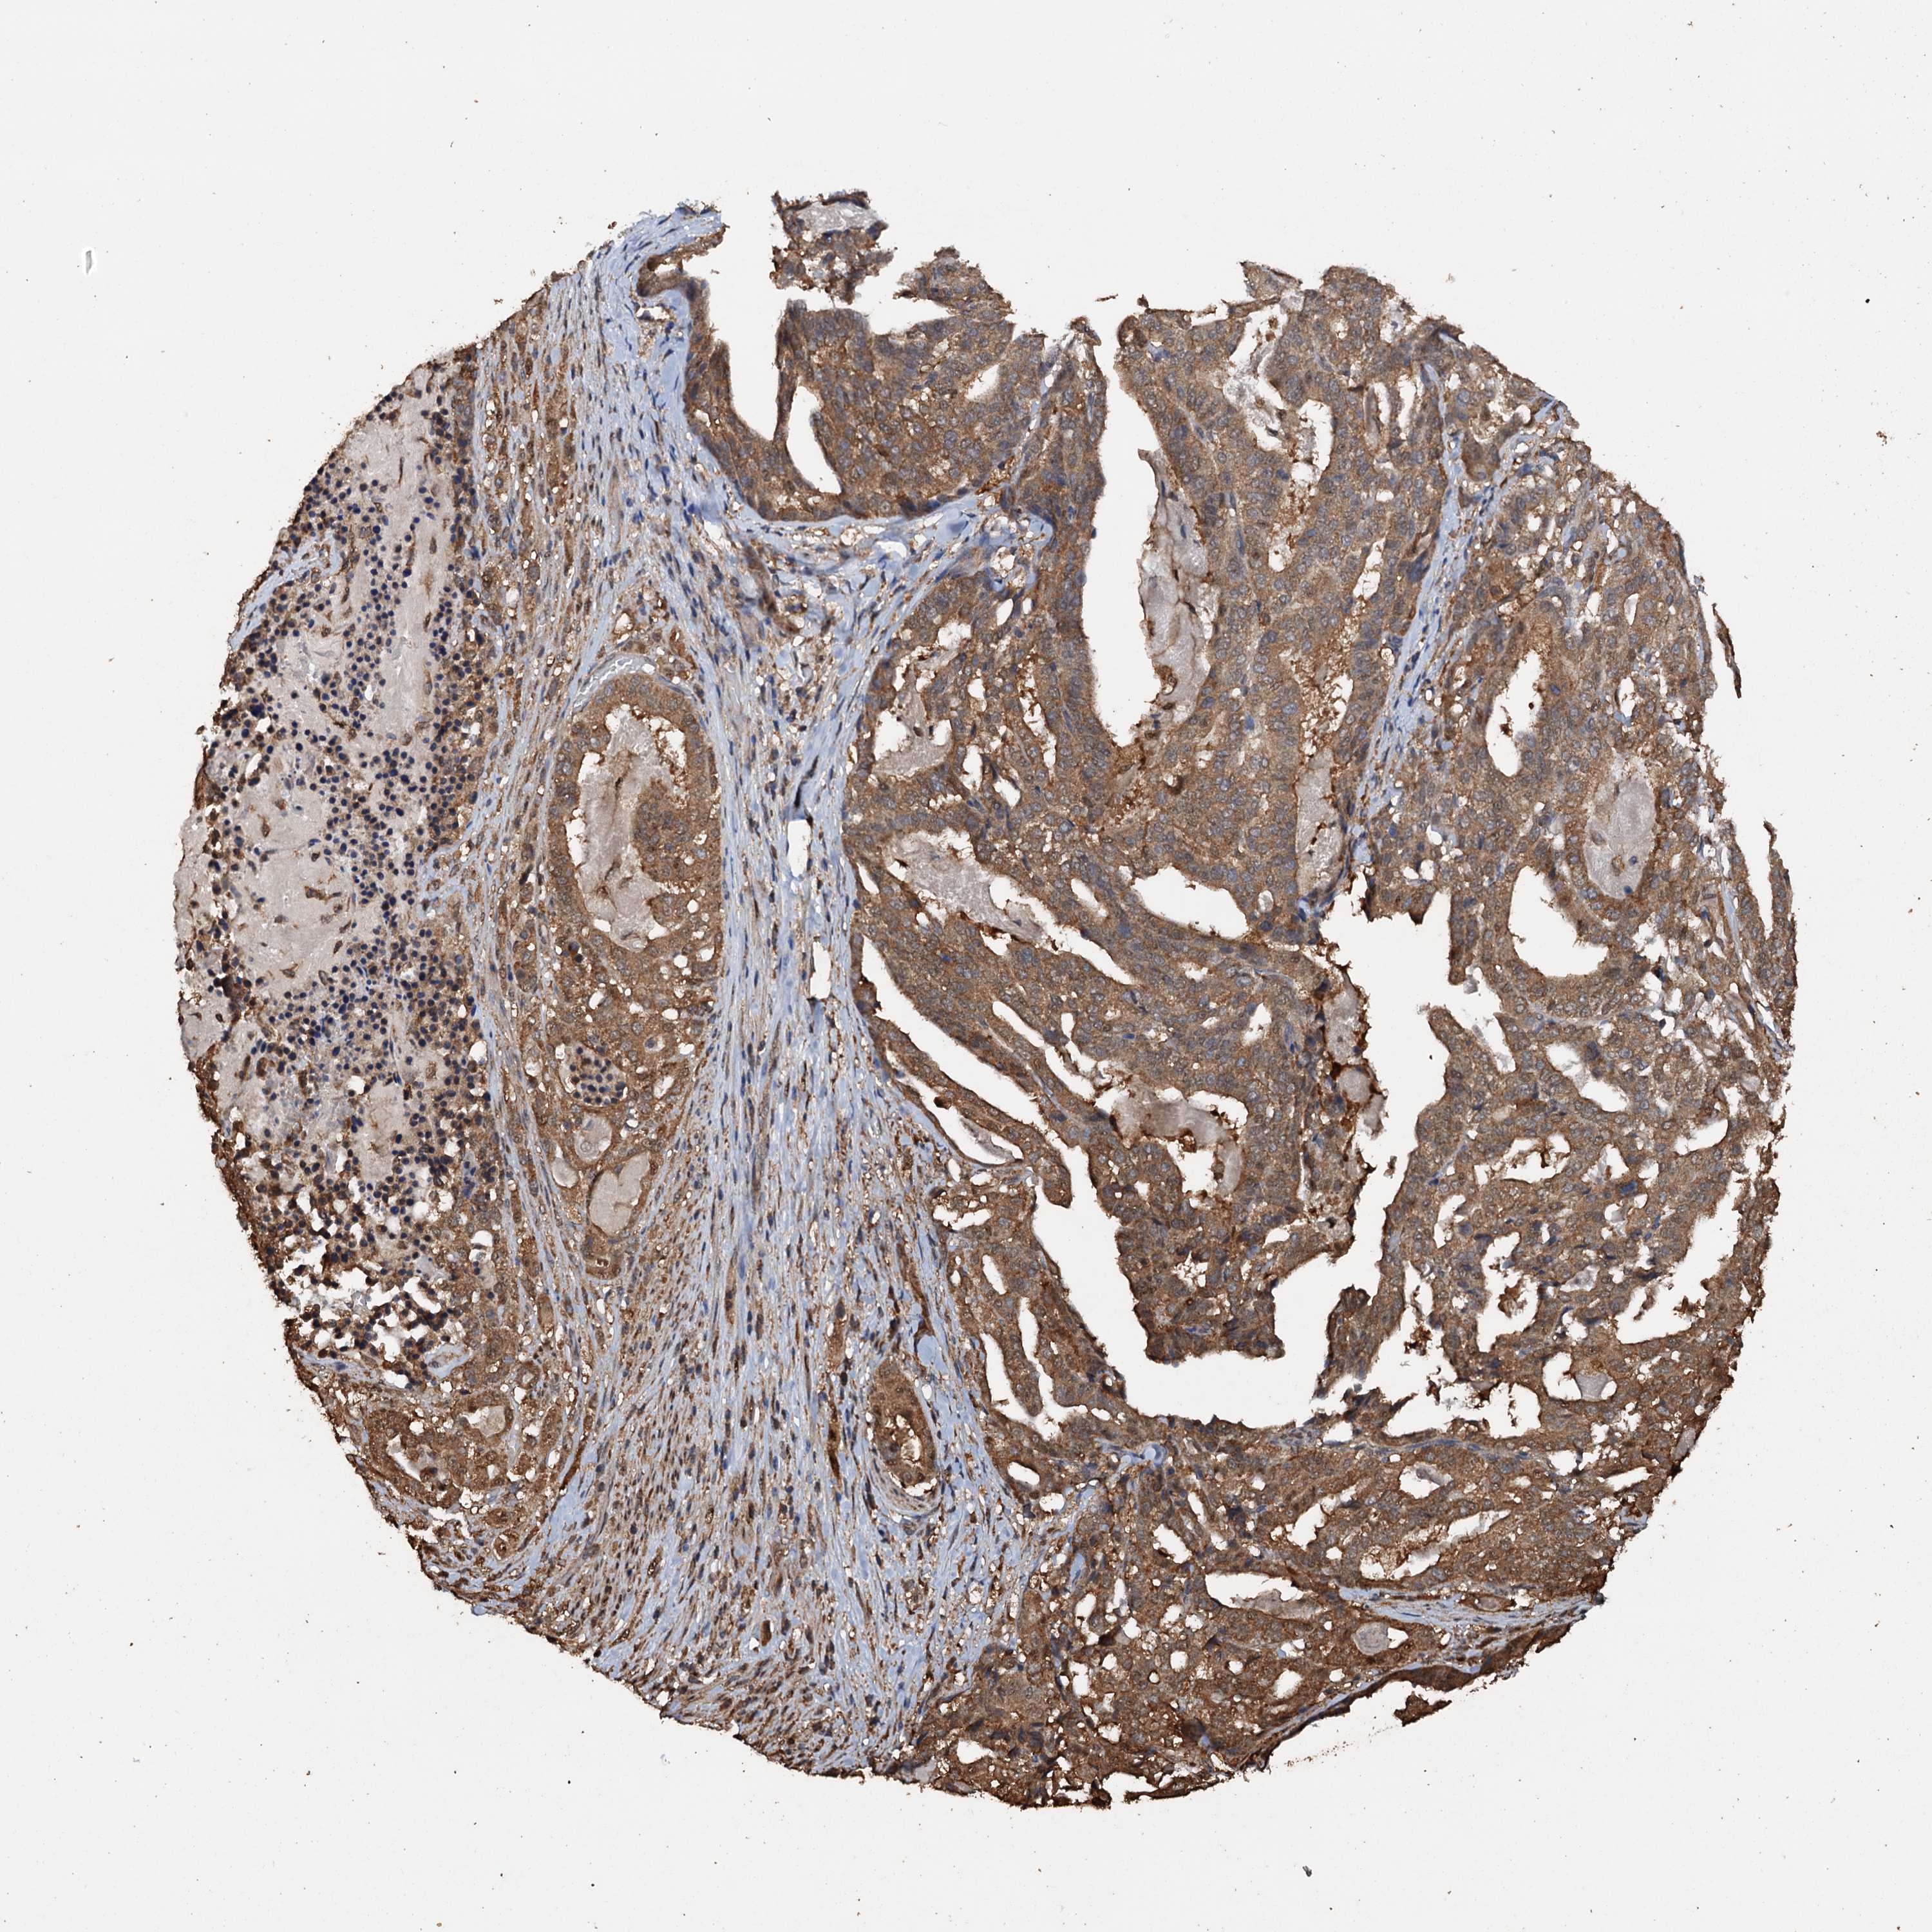

STOMACH CANCER - Protein expressioni

A mouse-over function shows sample information and annotation data. Click on an image to view it in a full screen mode. Samples can be filtered based on level of antibody staining by selecting one or several of the following categories: high, medium, low and not detected. The assay and annotation is described here.

Note that samples used for immunohistochemistry by the Human Protein Atlas do not correspond to samples in the TCGA dataset.

Antibody stainingi

Antibody staining in the annotated cell types in the current human tissue is reported as not detected, low, medium, or high, based on conventional immunohistochemistry profiling in selected tissues. This score is based on the combination of the staining intensity and fraction of stained cells.

Each image is clickable and will lead to virtual microscopy that enables deeper exploration of all samples and also displays staining intensity scores, fraction scores and subcellular localization as well as patient and tissue information for each sample.

Antibody HPA040512

Antibody HPA044220

Staining

High

Medium

Low

Not detected

Intensity

Strong

Moderate

Weak

Negative

Quantity

>75%

75%-25%

<25%

None

Location

Nuclear

Cytoplasmic/membranous

Cytoplasmic/membranous,nuclear

Adenocarcinoma, NOS

Adenocarcinoma, High grade